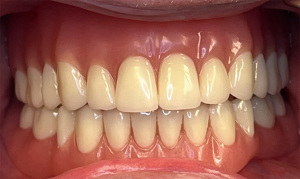

Fixed dental prosthesis

A fixed dental prosthesis is securely fixed to a natural tooth or teeth or dental implant(s) and cannot be removed by the patient. It can be used to restore teeth in partially edentulous arches or to restore clinical crown that is discolored, has abnormal or missing structure such as in amelogenesis imperfecta—a group of hereditary conditions that affect the structure and appearance of dental enamel (47) and ectodermal dysplasia patients respectively (Figure 5).

When a missing tooth for a partial edentulous patient, is to be replaced, a conventional fixed dental prosthesis or implant supported fixed prosthesis is usually the treatment of choice. However, when selecting a fixed replacement, there should be good periodontal health and no excessive soft/hard tissue deficiencies (4,48). In the event of significant soft/hard tissue deficiencies, a removable prosthesis may be indicated, although it may be possible to augment the deficient ridge with grafts.

A less invasive composite resin direct restorations are usually preferred in adolescence to avoid excessive teeth preparation of younger patients (Figure 6) (49). Longevity of composite resin restorations is significantly lower when used in patients with enamel hypoplasia compared to those with hypomineralized or hypomatured amelogenesis imperfecta (50). Indirect restorations such as crowns are preferred over direct restorations based on scientific evidence in patients with amelogenesis imperfecta (49).

Dental implants are commonly used in the oral reconstruction of ectodermal dysplasia patients with 20 years cumulative survival rate of 84.6% (51). Implant supported fixed prostheses can be provided for ectodermal dysplasia patients starting from fourteen years of age (7). However, additional clinical evidence is needed regarding bone resorption, the esthetic outcomes of implant therapy, and physiological considerations in ectodermal dysplasia patients (52).

It is known that palatal and alveolar bone deficiency cause relapse in orthodontic treatment of cleft lip and palate patients and late secondary bone grafting may not stabilize maxillary transverse dimension obtained by expansion (4). Therefore, permanent retention using prostheses is advised for some of these patients. Fixed dental prosthesis traversing the cleft can stabilize the premaxilla section, therefore preventing palatal expansion relapse. Implant placement is preferred after growth is over and placement is usually recommended within four to six months after bone grafting. Five-year survival rates for dental implant ranges from 80% to 90% (mean 88.6%). This shows that dental implant in cleft lip and palate patients have high success rate and allow for sufficient oral rehabilitation. However, evidence is limited since there are limited prospective clinical studies on dental implant in cleft patients (53).